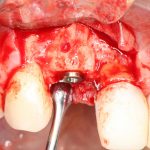

Наложение швов.

Если на этапе разреза и формирования раны всё сделано правильно, то наложение швов не вызывает особых трудностей. Периостотомия или послабляющие разрезы на периосте не требуются (ни практически никогда не требуются). А сами швы получаются аккуратными и герметичными:

Обрати внимание, что все шовные лигатуры находятся в пределах кератинизированной десны. Это позволяет избежать деформации тканей и лишних рубцов. В наиболее уязвимых местах (около зубов) шовные лигатуры лучше продублировать.